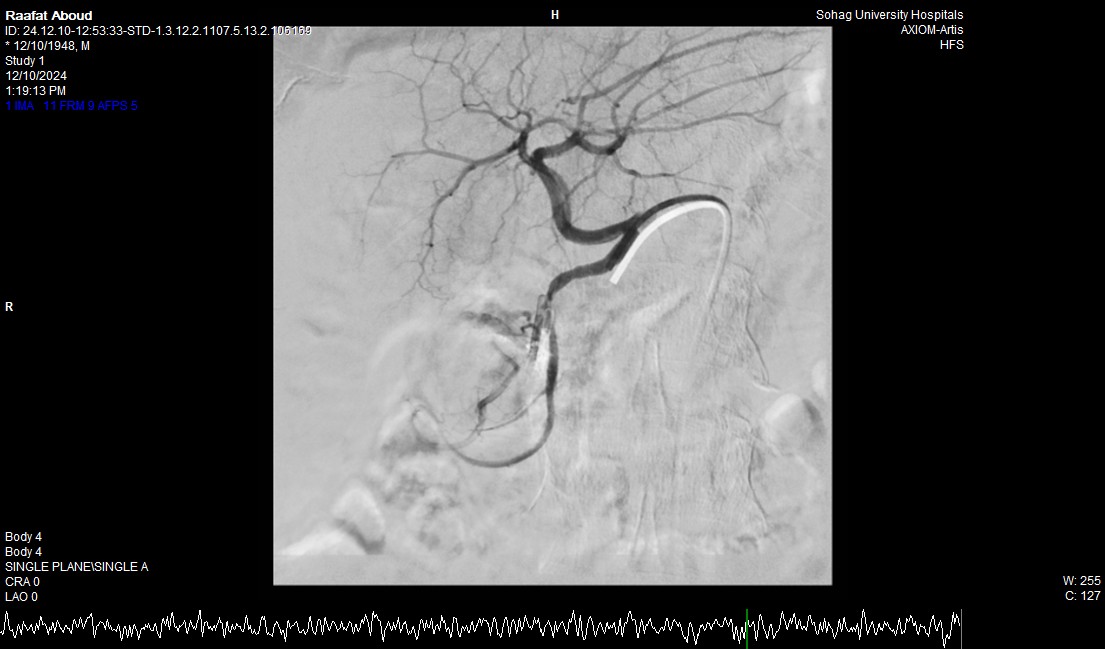

جامعة سوهاج.. وفي خطوة لاحقة، تم استدعاء فريق الأشعة التداخلية الذي تمكن من إغلاق الشريان النازف بشكل عاجل باستخدام جهاز القسطرة، ما ساهم في استقرار حالة المريض.

جامعة سوهاج.. أكد الدكتور محمد زاكي، رئيس قسم الأشعة، أن مثل هذه الحالات تعد من أخطر الطوارئ الطبية، حيث يتطلب التعامل معها إجراء قسطرة شريانية عاجلة لإيقاف النزيف. وأضاف أن وحدة الأشعة التداخلية مزودة بجهاز أشعة محوري متقدم مخصص لمثل هذه التدخلات، مشيرًا إلى أن هذا النجاح يعكس التعاون المثمر بين أقسام المستشفى المختلفة ووحدة الأشعة التداخلية لتقديم خدمات متميزة للمرضى.